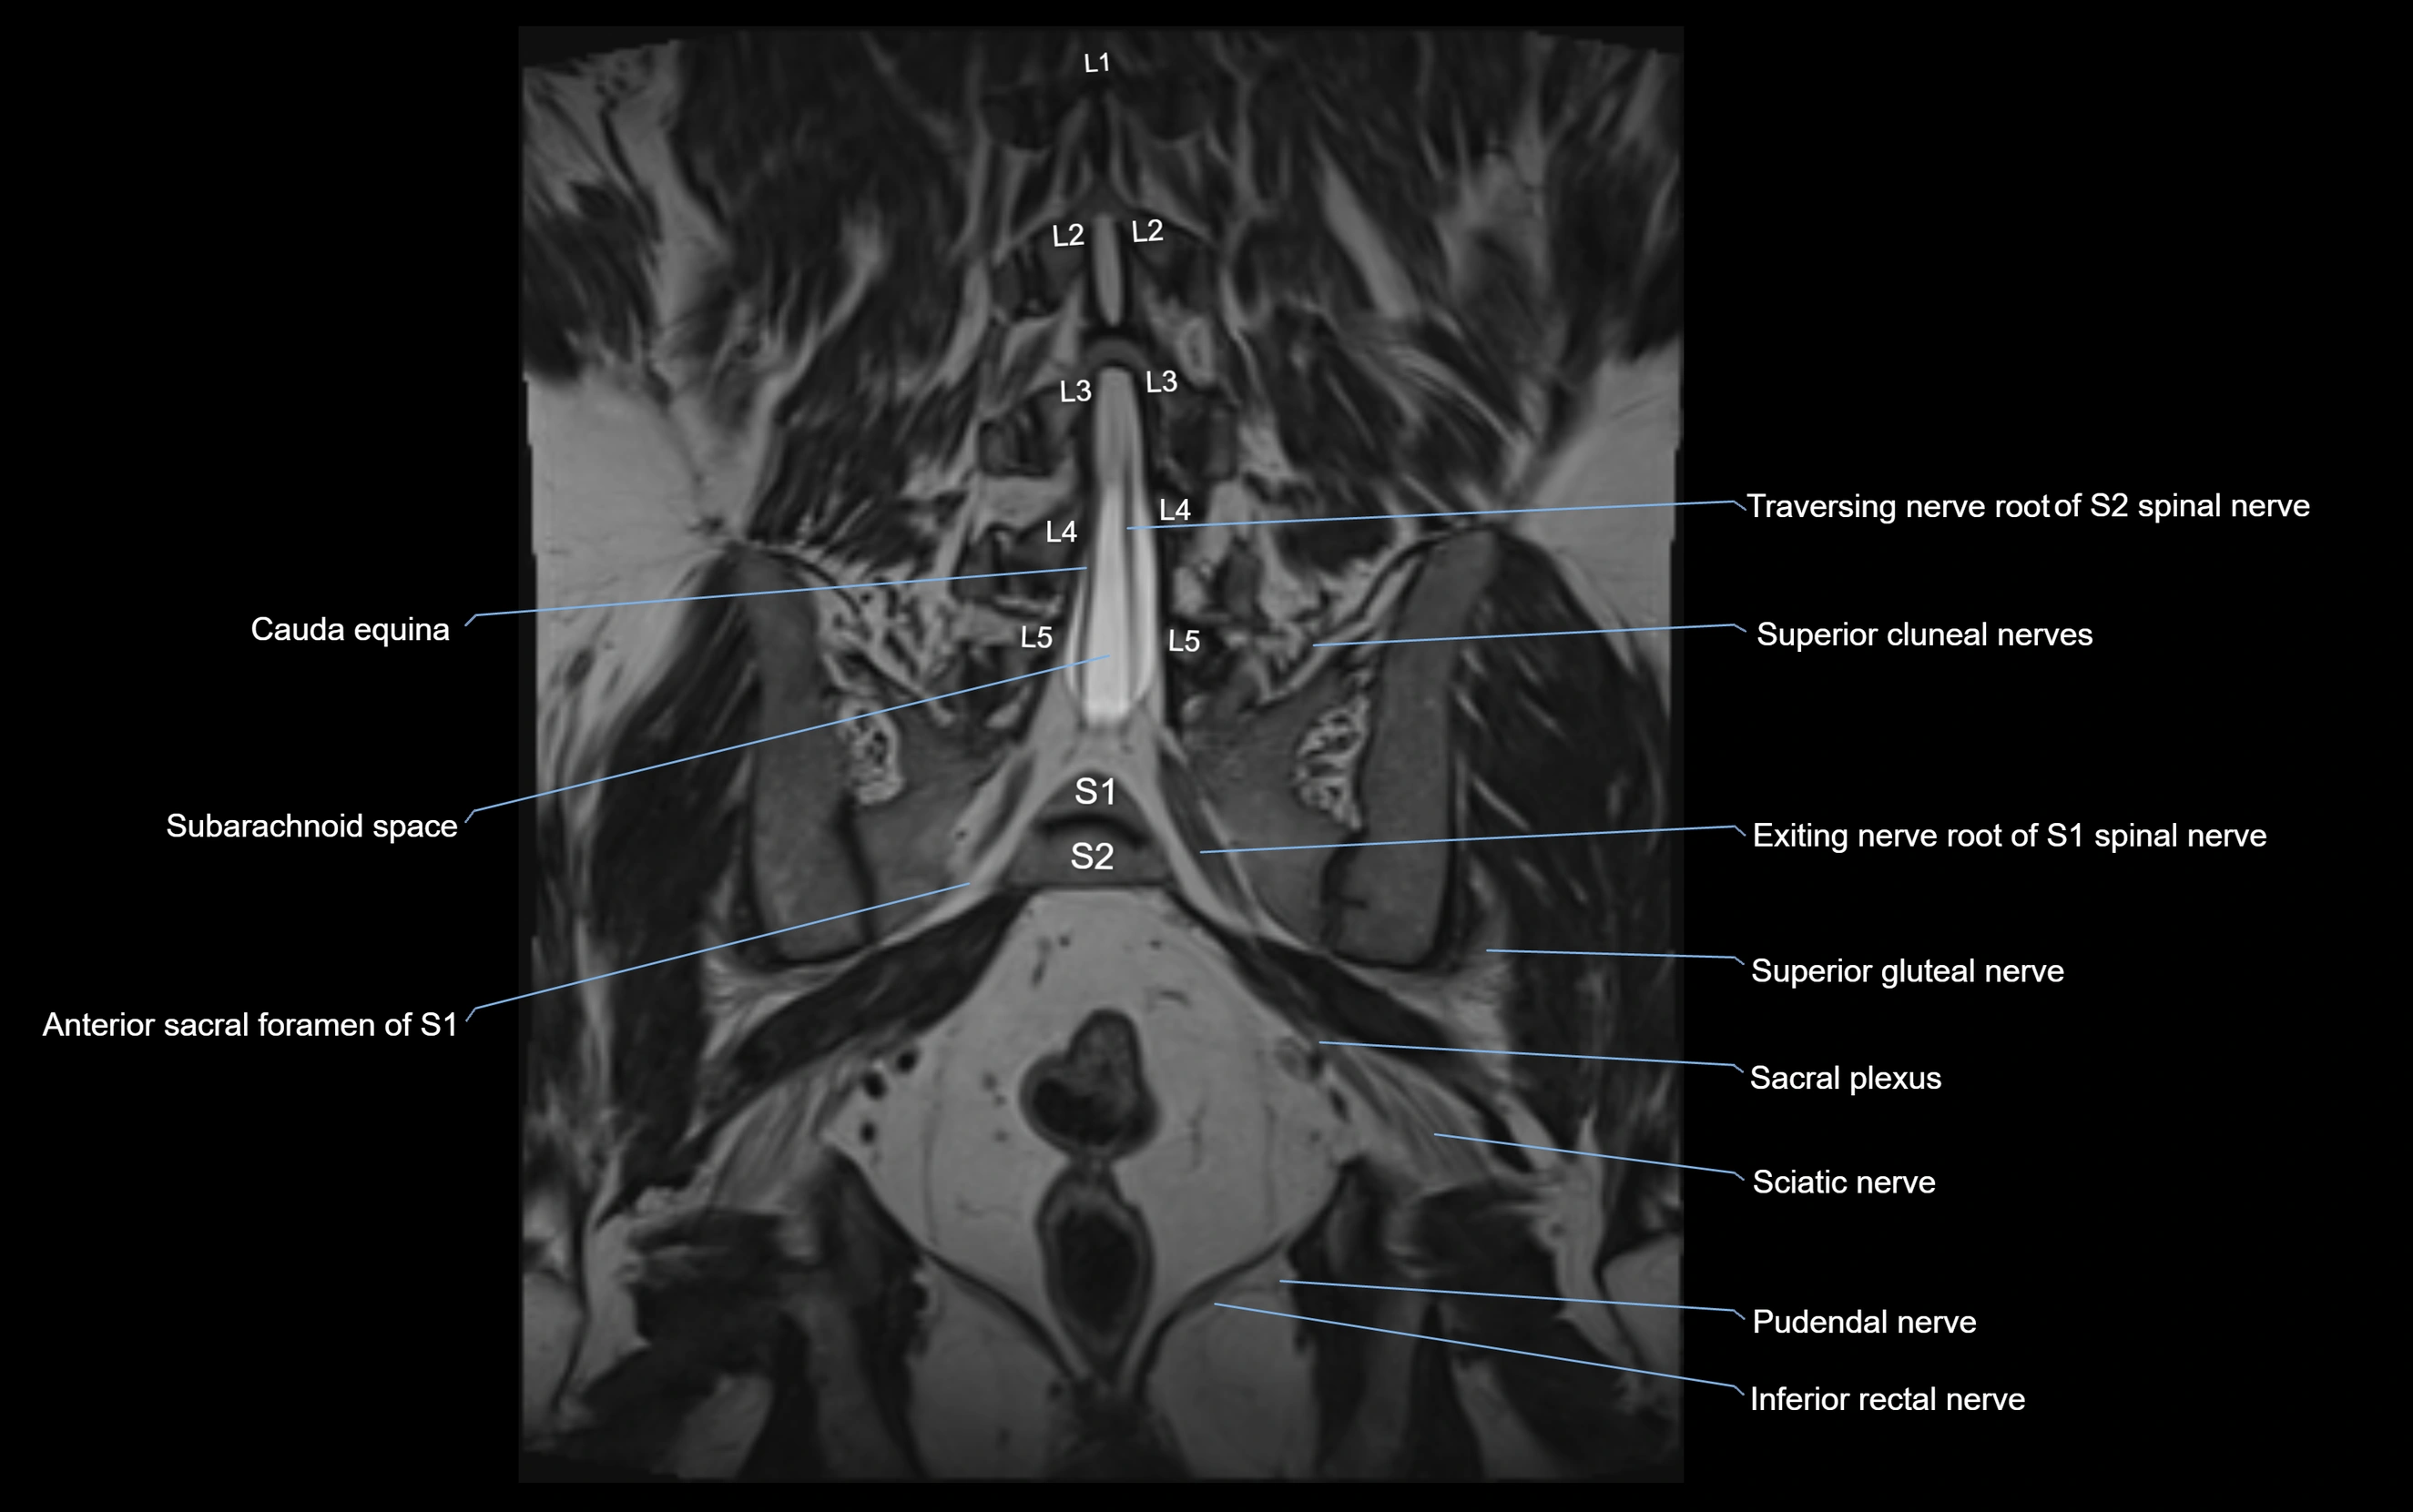

MRI image

image